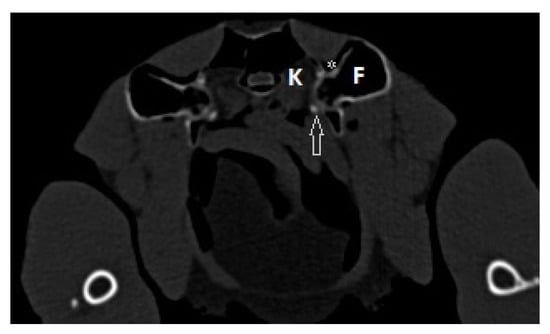

2.2. Surgical Procedure and Post-Surgery Management